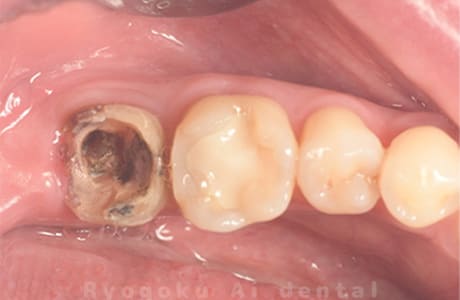

Case16

-

- 原因

- 重度カリエス

- 治療内容

- マイクロエンド

- 治療費用

- 77,000円(被せ物の費用は別途)

- 担当医

- Dr. 炭野

歯が欠けたとのことでご来院された患者様です。神経まで虫歯が及んでいたため、神経を除去し、治療を行いました。経過良好です。